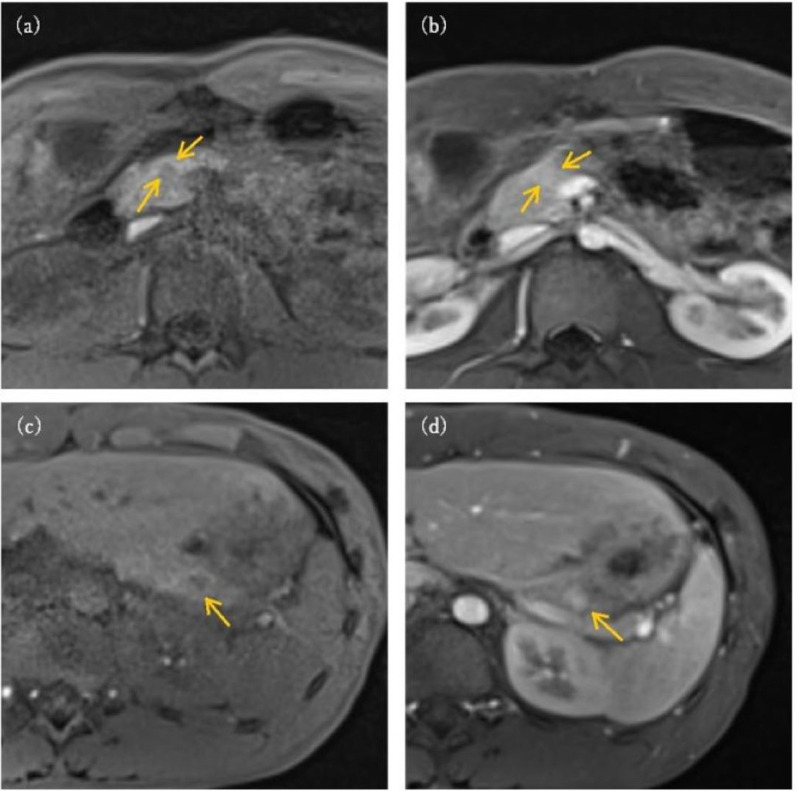

Multiple endocrine neoplasia type 1 (MEN1) is an autosomal dominant disorder attributed to mutations in the MEN1 gene and is characterized by multiple endocrine tumors, including insulinoma. Asymptomatic hyperinsulinemic hypoglycemia and pancreatic nodules were incidentally detected in a 14-yr-old male carrying a pathogenic MEN1 variant. Although insulinoma was suspected, it did not meet Whipple's triad, the classic diagnostic criteria for insulinoma, and some hypoglycemic provocation tests were negative. Selective arterial secretagogue injection (SASI) testing strongly suggested the presence of an insulinoma, and the lesions were surgically excised. The pathological findings were consistent with the SASI test results. Diagnosis of insulinoma based on conventional tests is challenging in some patients with asymptomatic insulinoma, and SASI testing can be useful not only for localization but also for insulinoma diagnosis.